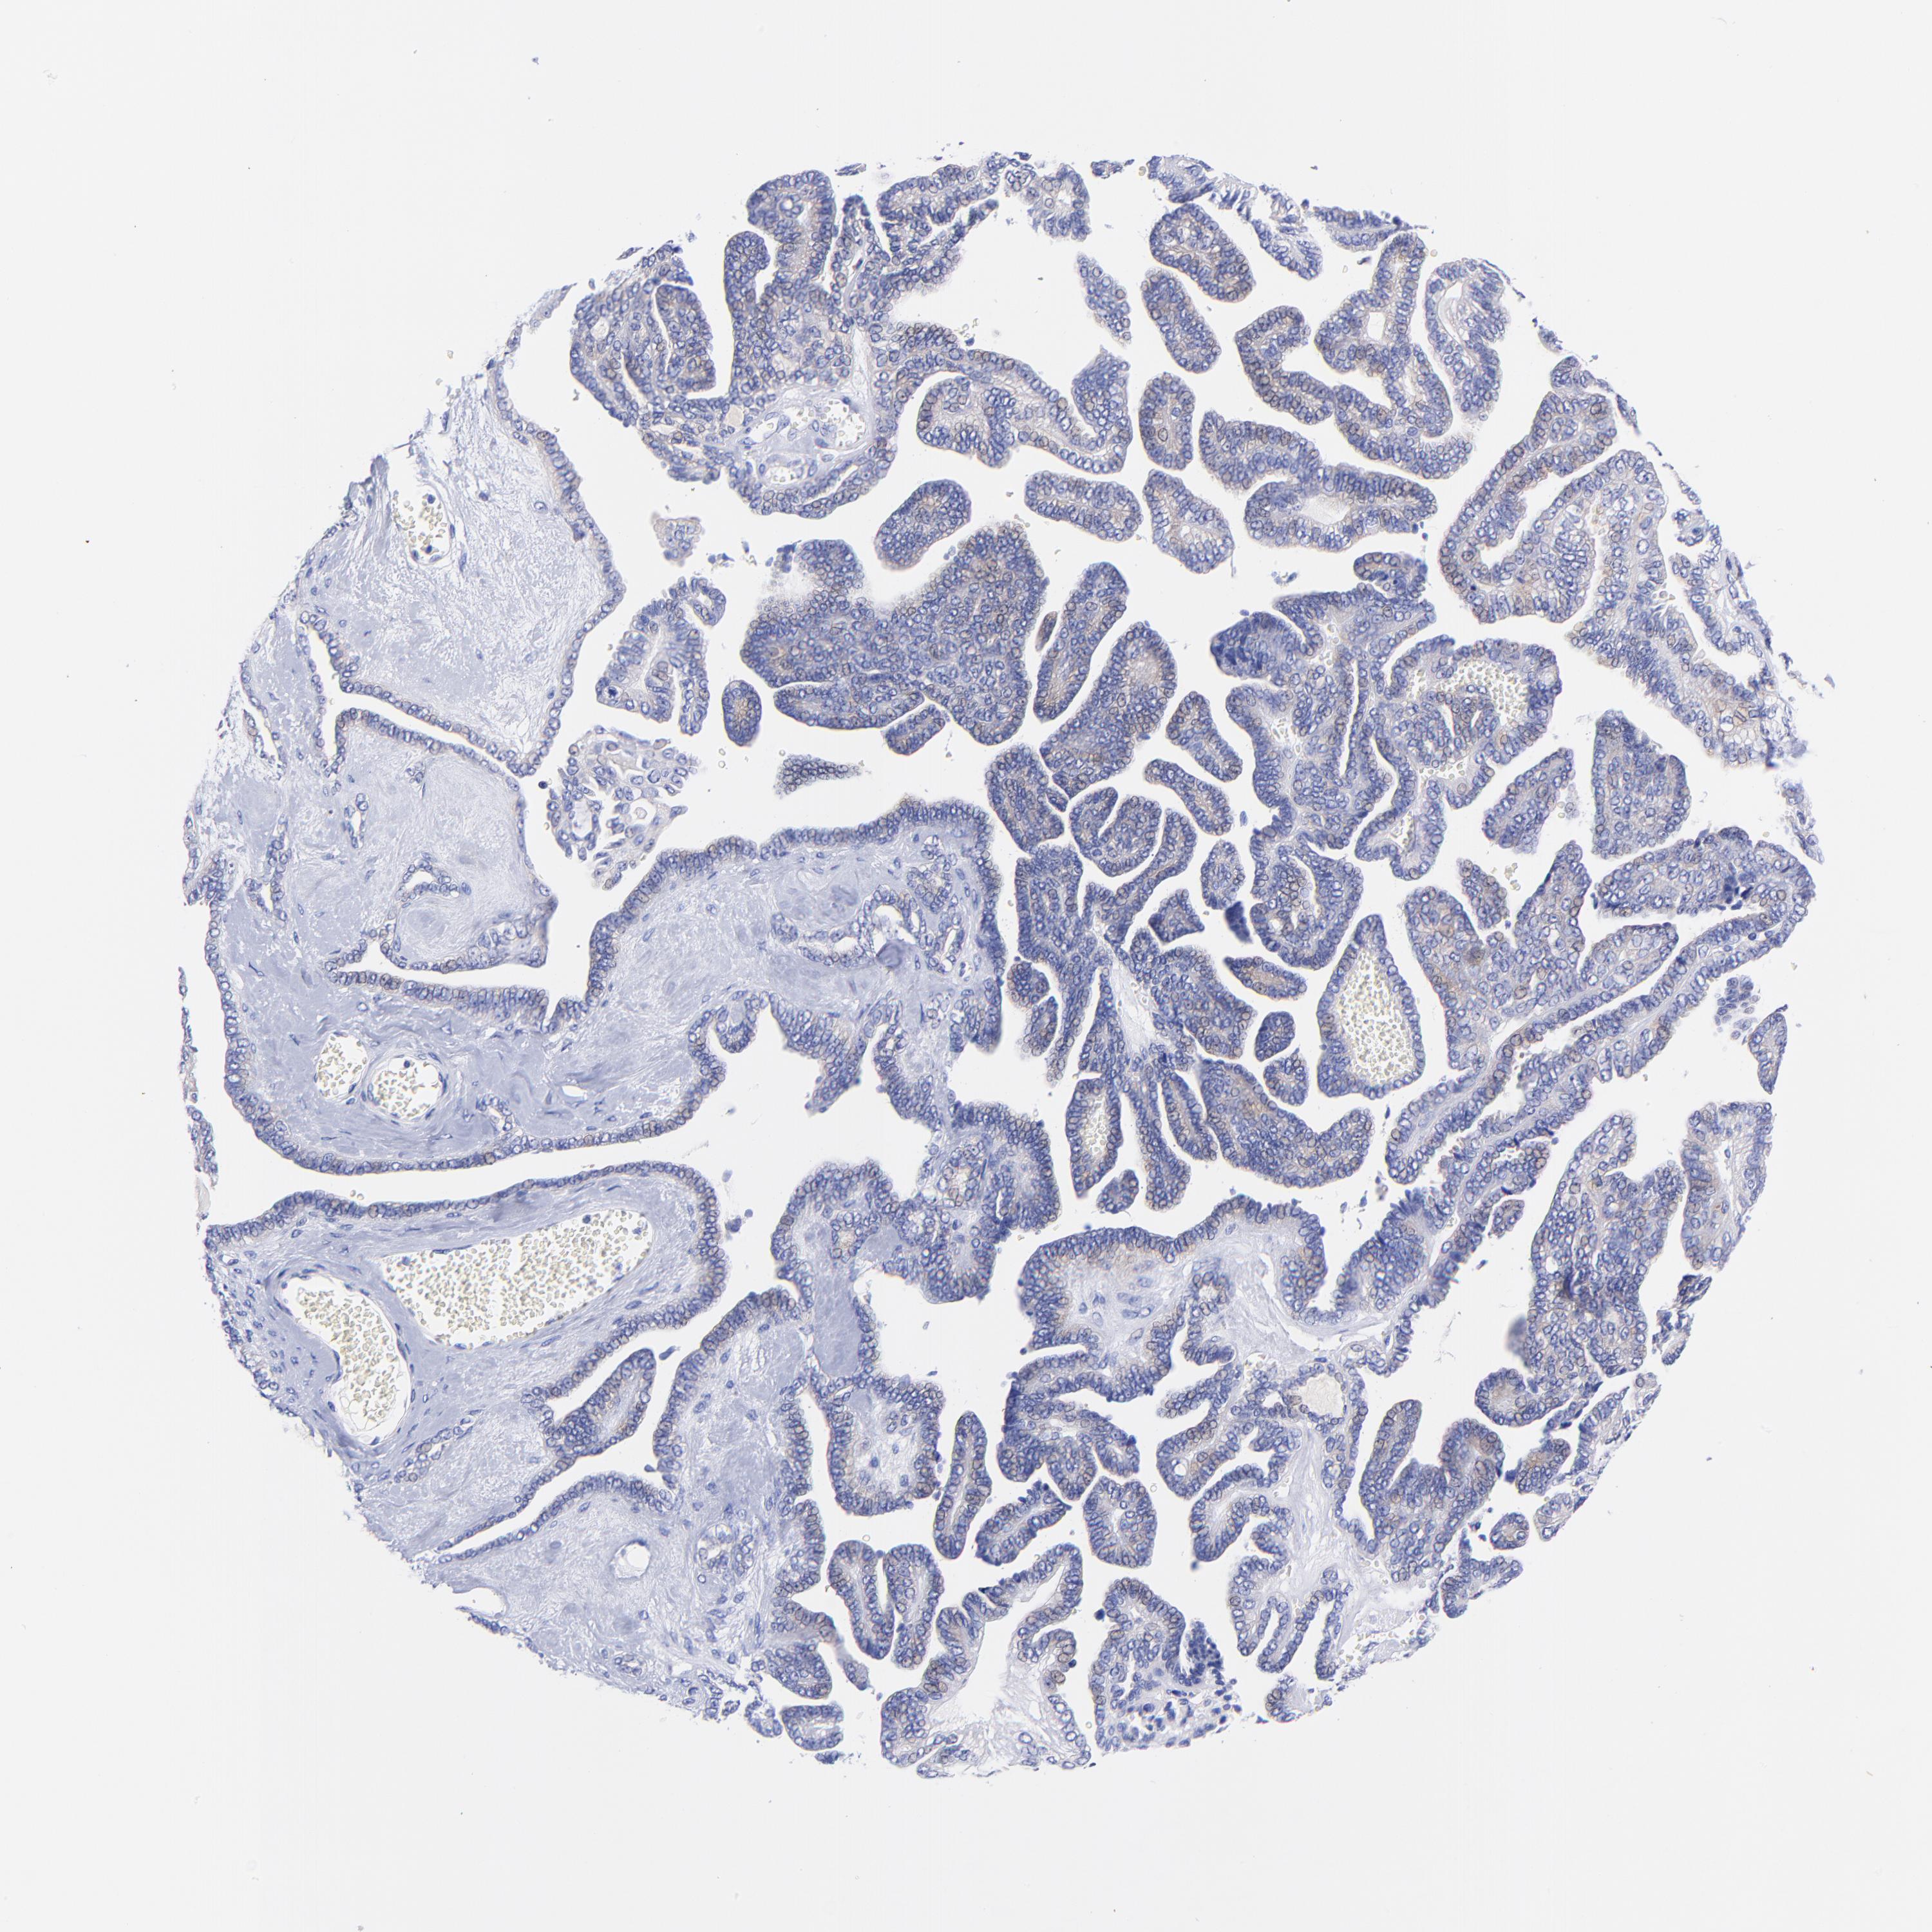

OVARIAN CANCER - Protein expressioni

A mouse-over function shows sample information and annotation data. Click on an image to view it in a full screen mode. Samples can be filtered based on level of antibody staining by selecting one or several of the following categories: high, medium, low and not detected. The assay and annotation is described here.

Note that samples used for immunohistochemistry by the Human Protein Atlas do not correspond to samples in the TCGA dataset.

Antibody stainingi

Antibody staining in the annotated cell types in the current human tissue is reported as not detected, low, medium, or high, based on conventional immunohistochemistry profiling in selected tissues. This score is based on the combination of the staining intensity and fraction of stained cells.

Each image is clickable and will lead to virtual microscopy that enables deeper exploration of all samples and also displays staining intensity scores, fraction scores and subcellular localization as well as patient and tissue information for each sample.

Antibody HPA003116

Antibody HPA024694

Antibody CAB004419

Cystadenocarcinoma, mucinous, NOS

Carcinoma, endometroid

Cystadenocarcinoma, serous, NOS

Carcinoma, NOS